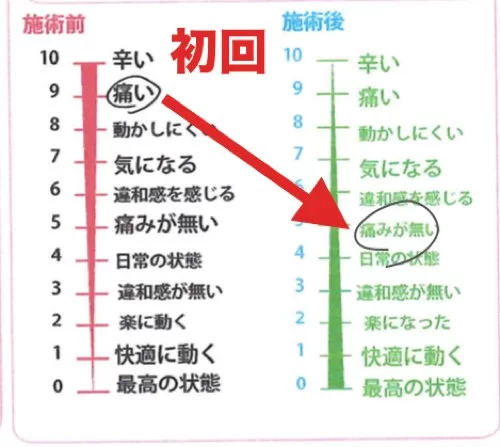

施術前後のアンケート

施術前 9:痛い → 施術後 5:痛みが無い

2ヶ月間消えなかった痛みは初回の施術後に消えましたが

2ヶ月ものあいだ硬直していた筋肉や腱はクセがついていて

元の悪い状態に戻りやすいので

もう何回かしっかり施術を受けに来て頂くことにしました。